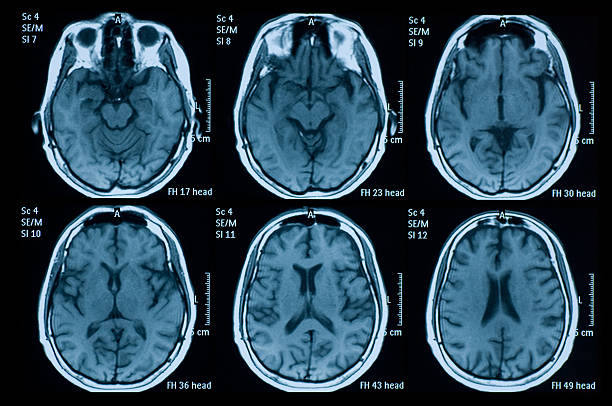

① 뇌·뇌혈관 MRI

- 적용 대상: 뇌질환이 의심되는 신경학적 이상 증상이 있거나, 관련 질환(뇌경색, 뇌종양 등)이 확인된 경우.

- 참고: 단순 두통이나 어지럼증만으로는 보험 적용이 어려울 수 있으나, 의사의 소견에 따라 뇌질환 위험도가 높다고 판단되면 혜택을 받을 수 있습니다.